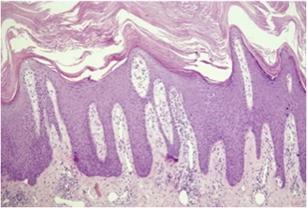

Fig. 1